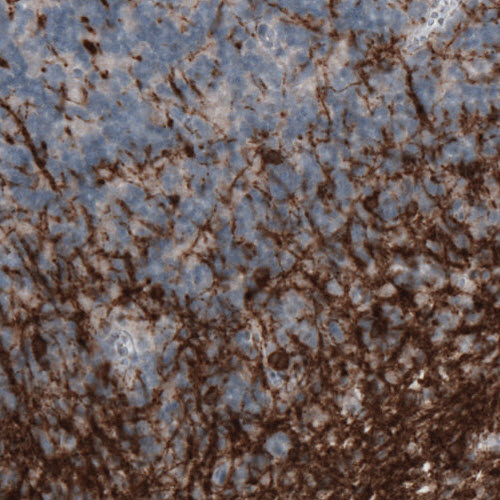

Immunohistochemical staining of rat cerebral cortex shows moderate immunoreactivity in oligodendrocytes.